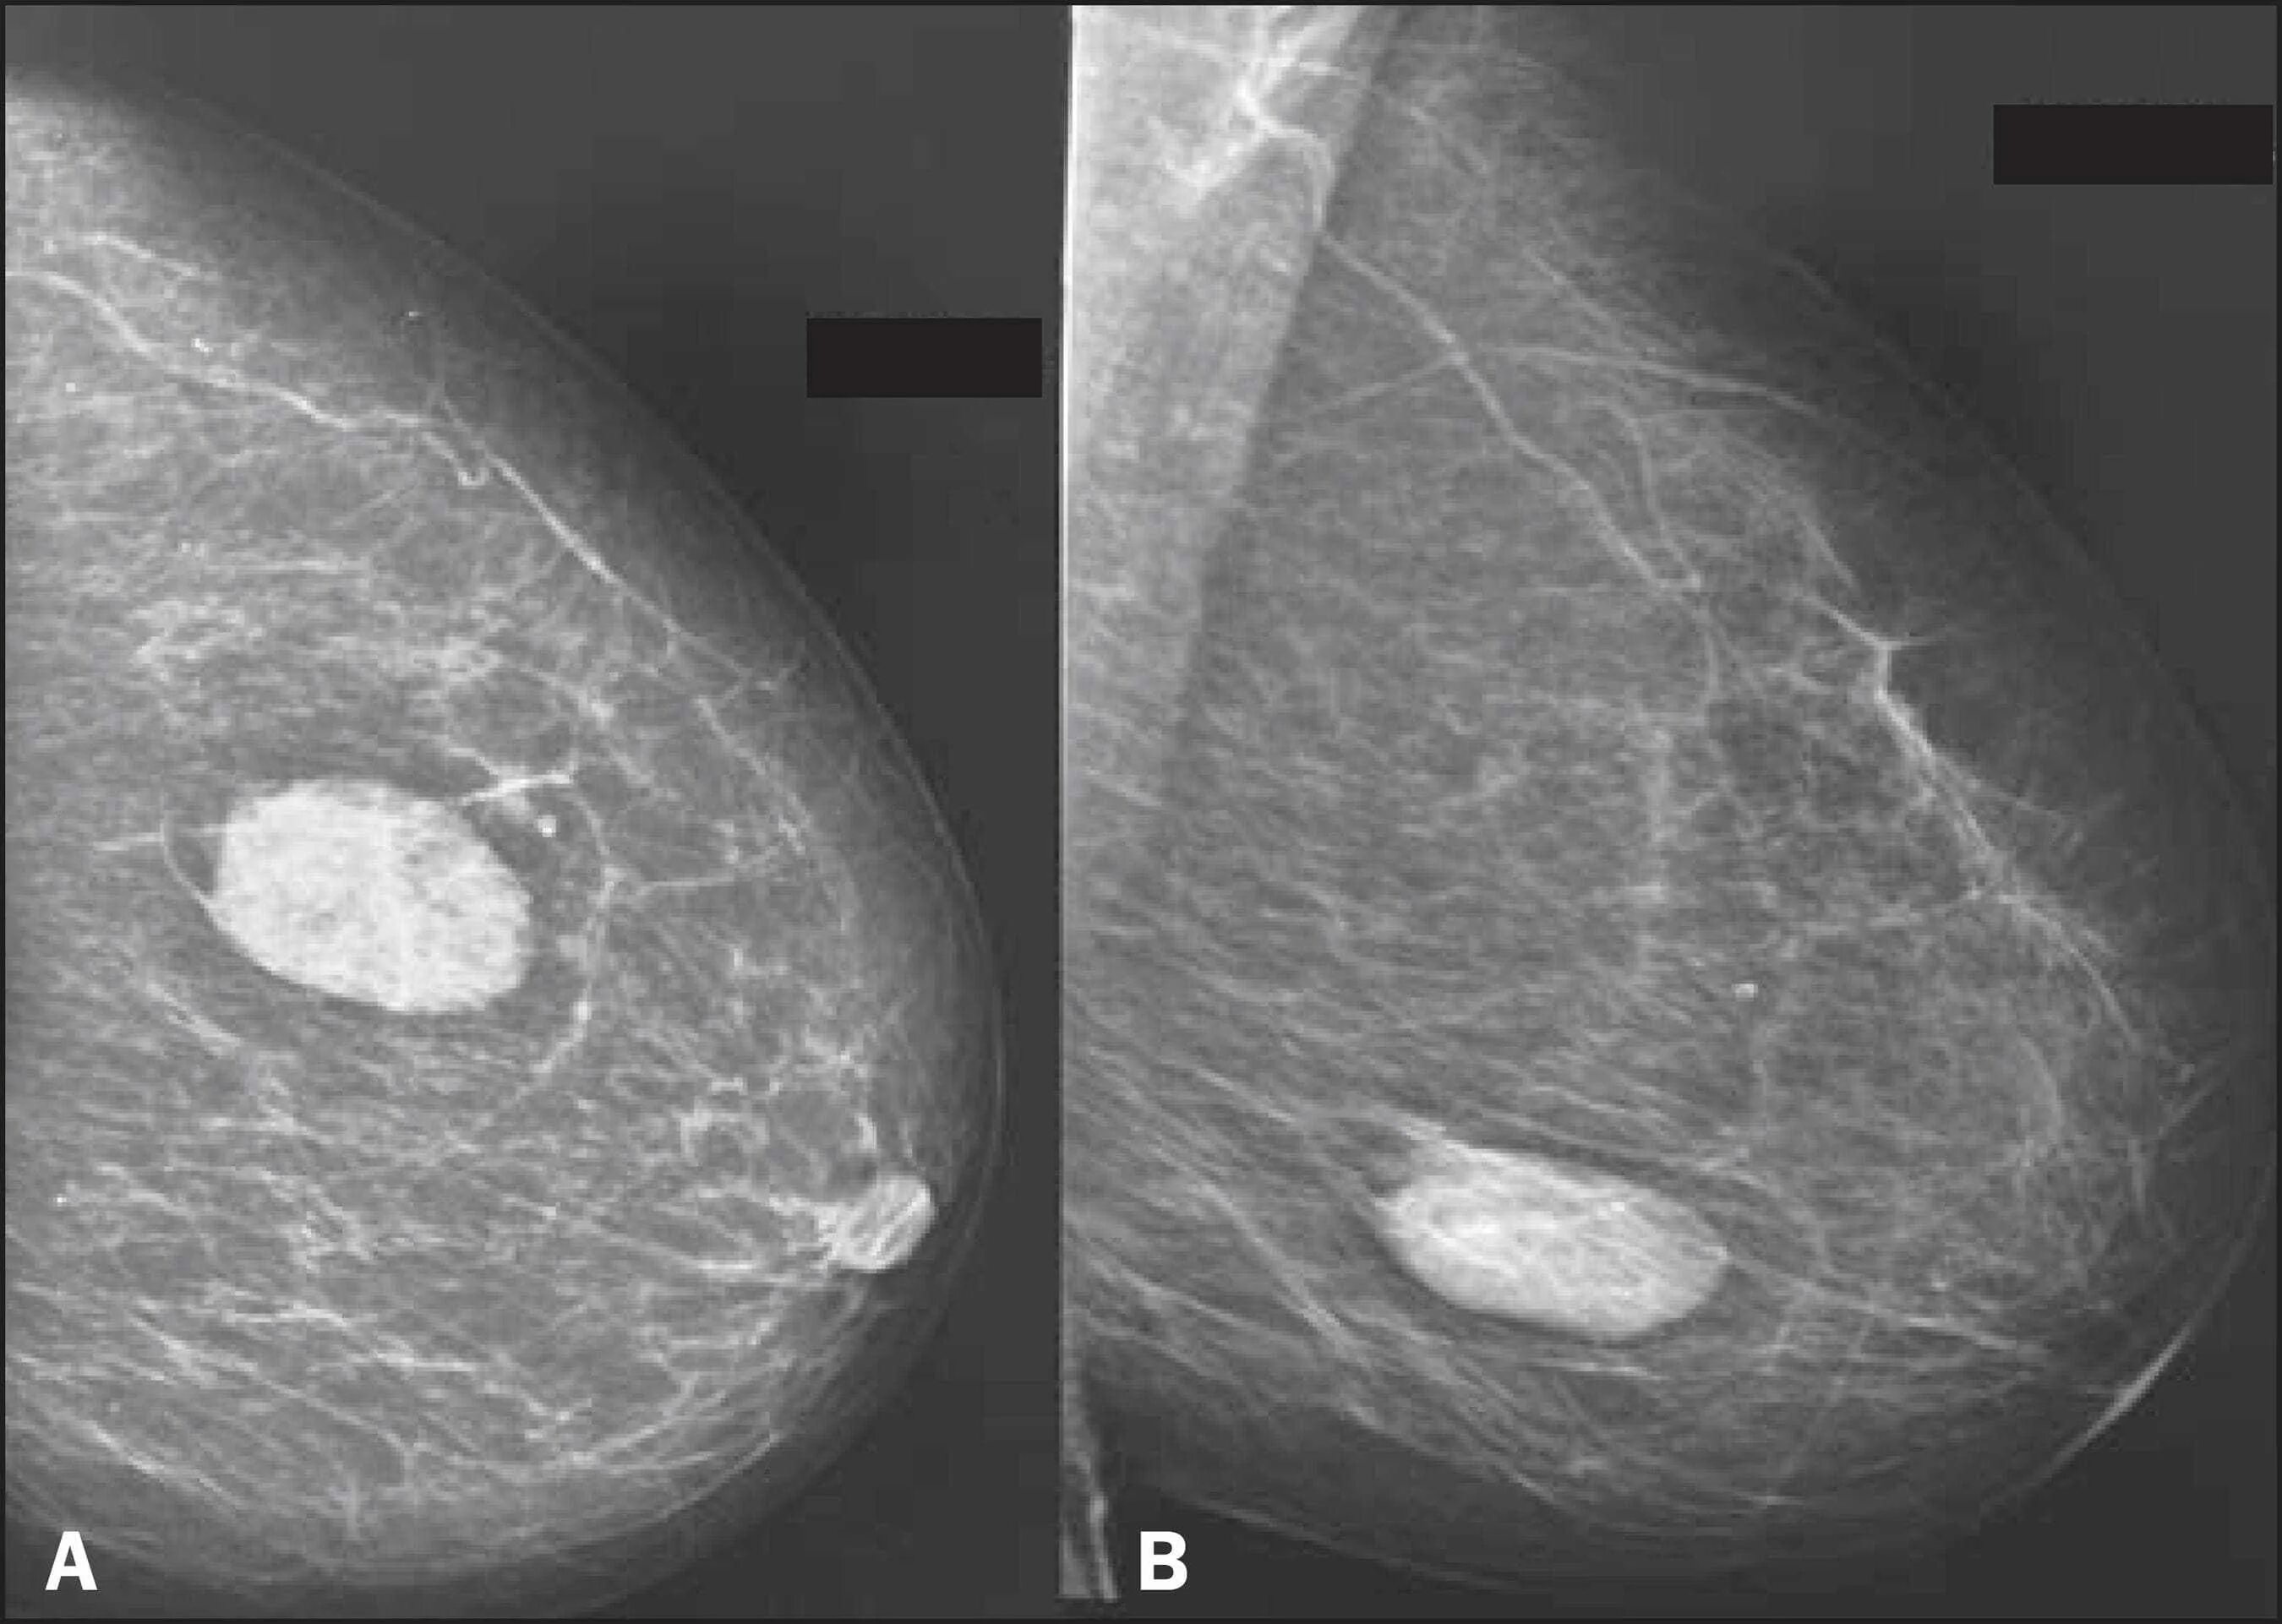

Доброкачественное новообразование молочной железы